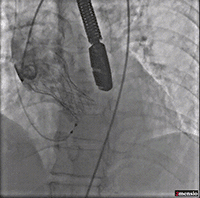

术前冠脉造影

主动脉根部造影